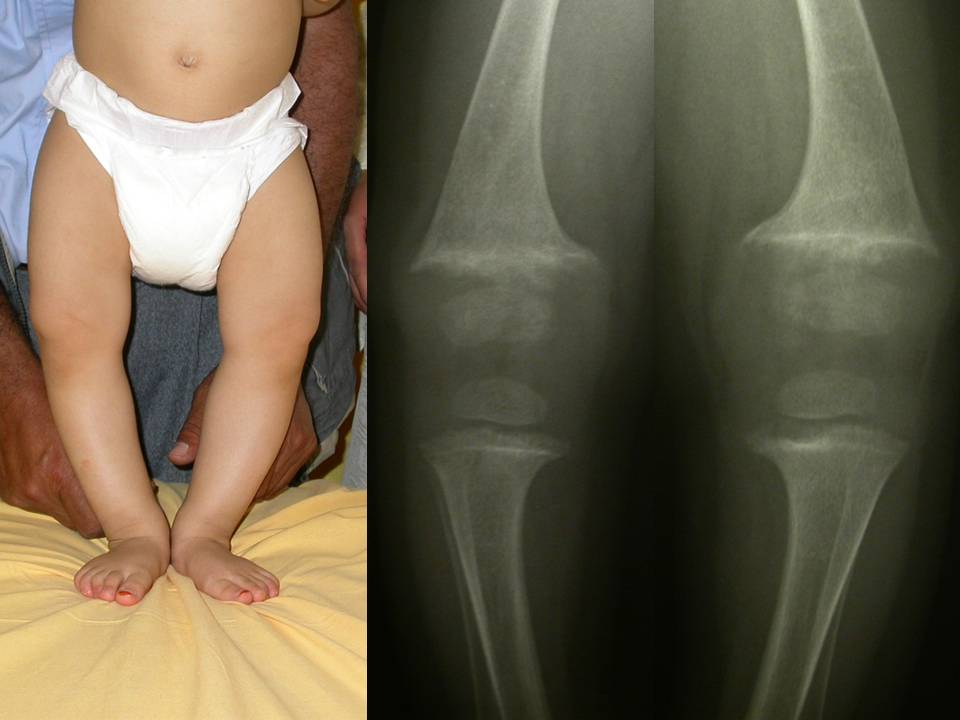

Fig 8. Rachitismo carenziale florido

Fig. 8: rachitismo carenziale florido